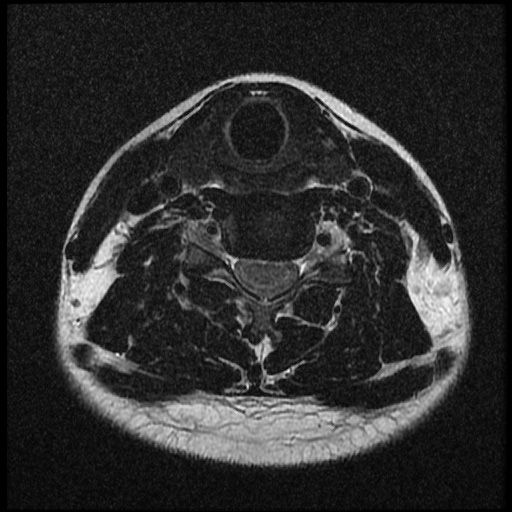

근대 21년 사고 이후부터 목쪽이 계속 아픈 상태 여서 사고로 인한 급성인지 우연이 겹친 민성 디스크 인지 확인하고 싶습니다~

이 MRI 사진은 21년도 사고 당시 찍은 MRI 사진 입니다. 확인 부탁드립니다~

전체 mri를 다 봐여겠지만 보여주신 mri 컷에서는 의미있는 경추 디스크탈출이 보이지 않습니다.